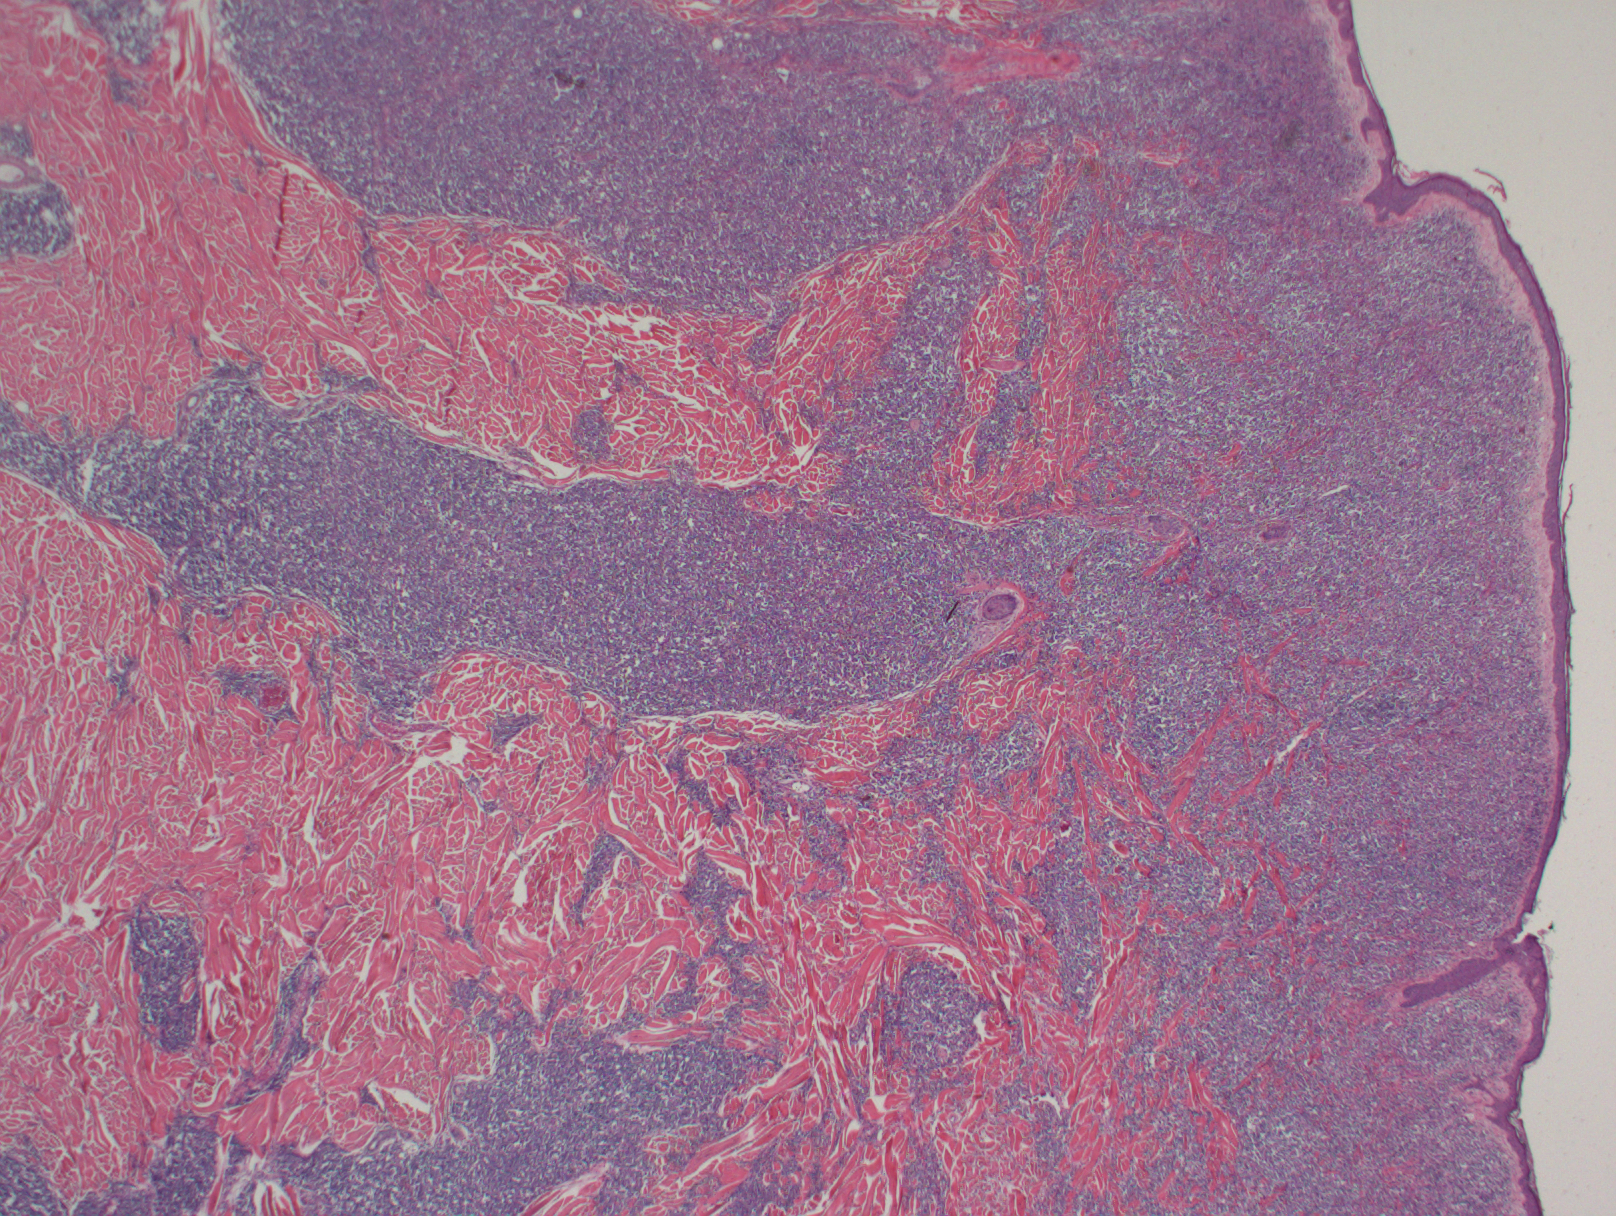

形态学:肿瘤细胞呈现弥漫生长,具母细胞特征(可类似淋巴母细胞或髓系母细胞):中等大小、形态单一、核轻度不规则、染色质细腻、一到多个核仁、胞质细少,无颗粒。在皮肤,通常浸润真皮,最终延及皮下,但不累及表皮;在骨髓,呈现稀少或成片间质浸润,涂片有时可见肿瘤细胞有膜下微小空泡及包膜伪足;在淋巴结,常侵犯髓区或滤泡间(白血病侵犯模式)。一般不出现凝固性坏死和血管中心性浸润。